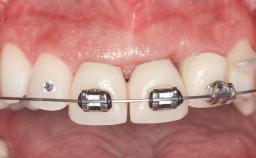

In 2001, a 48-year-old woman presented at a dental clinic with a failing fixed partial denture spanning from teeth 13 to 21. She was experiencing pain upon function, tenderness to palpation facial to tooth 13, and severe mobility of the prosthesis. Radiographic and clinical assessment revealed a subcrestal fracture of tooth 13, making its restoration unlikely. It was determined by the clinician that the tooth needed to be extracted prior to proceeding any further with dental care. After the extraction, the patient lost confidence in the progression of her treatment and sought consultation at the Center for Implant Dentistry. At her consultation visit in our clinic, an extra- and intraoral clinical examination revealed a medium lip line at full smile and an edentulous area spanning from 13 to 12 with both vertical and horizontal deficits in hard and soft tissue.

Width of Edentulous Span 1 tooth (>= 7 mm) 1 tooth (< 7 mm) 2 teeth or more

Soft Tissue Anatomy Intact Defective

Bone Volume Horizontally and vertically sufficient Horizontally deficient Deficient vertically or deficient vertically AND horizontally